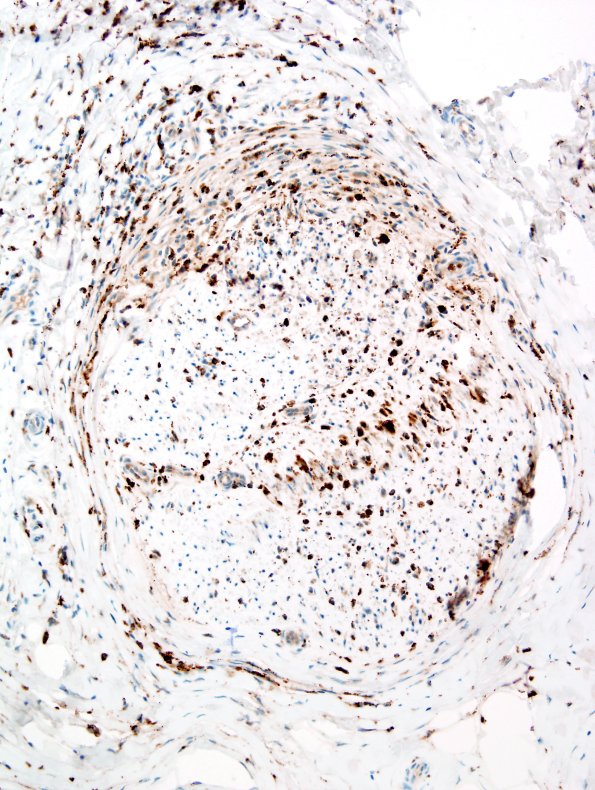

The endoneurium and perineurium contain numerous macrophages. (CD68 IHC)